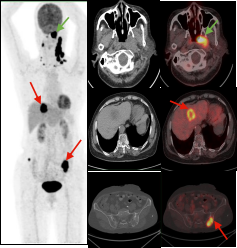

鼻咽癌全身转移:PET/CT显像示鼻咽左侧高代谢软组织肿块(绿色箭头);病理证实鼻咽非角化上皮癌,双侧颈部、肝脏及双侧髂骨多发转移瘤(红色箭头)。

胰腺癌全身转移:胰腺体尾部胰腺癌(绿色箭头),肝脏多发转移瘤及胸9椎体转移瘤(红色箭头)。

双癌检出:通过PET/CT一站式检查,同时检出两种肿瘤:甲状腺癌(绿色箭头)及子宫内膜癌(红色箭头),有利于临床治疗方案选择。